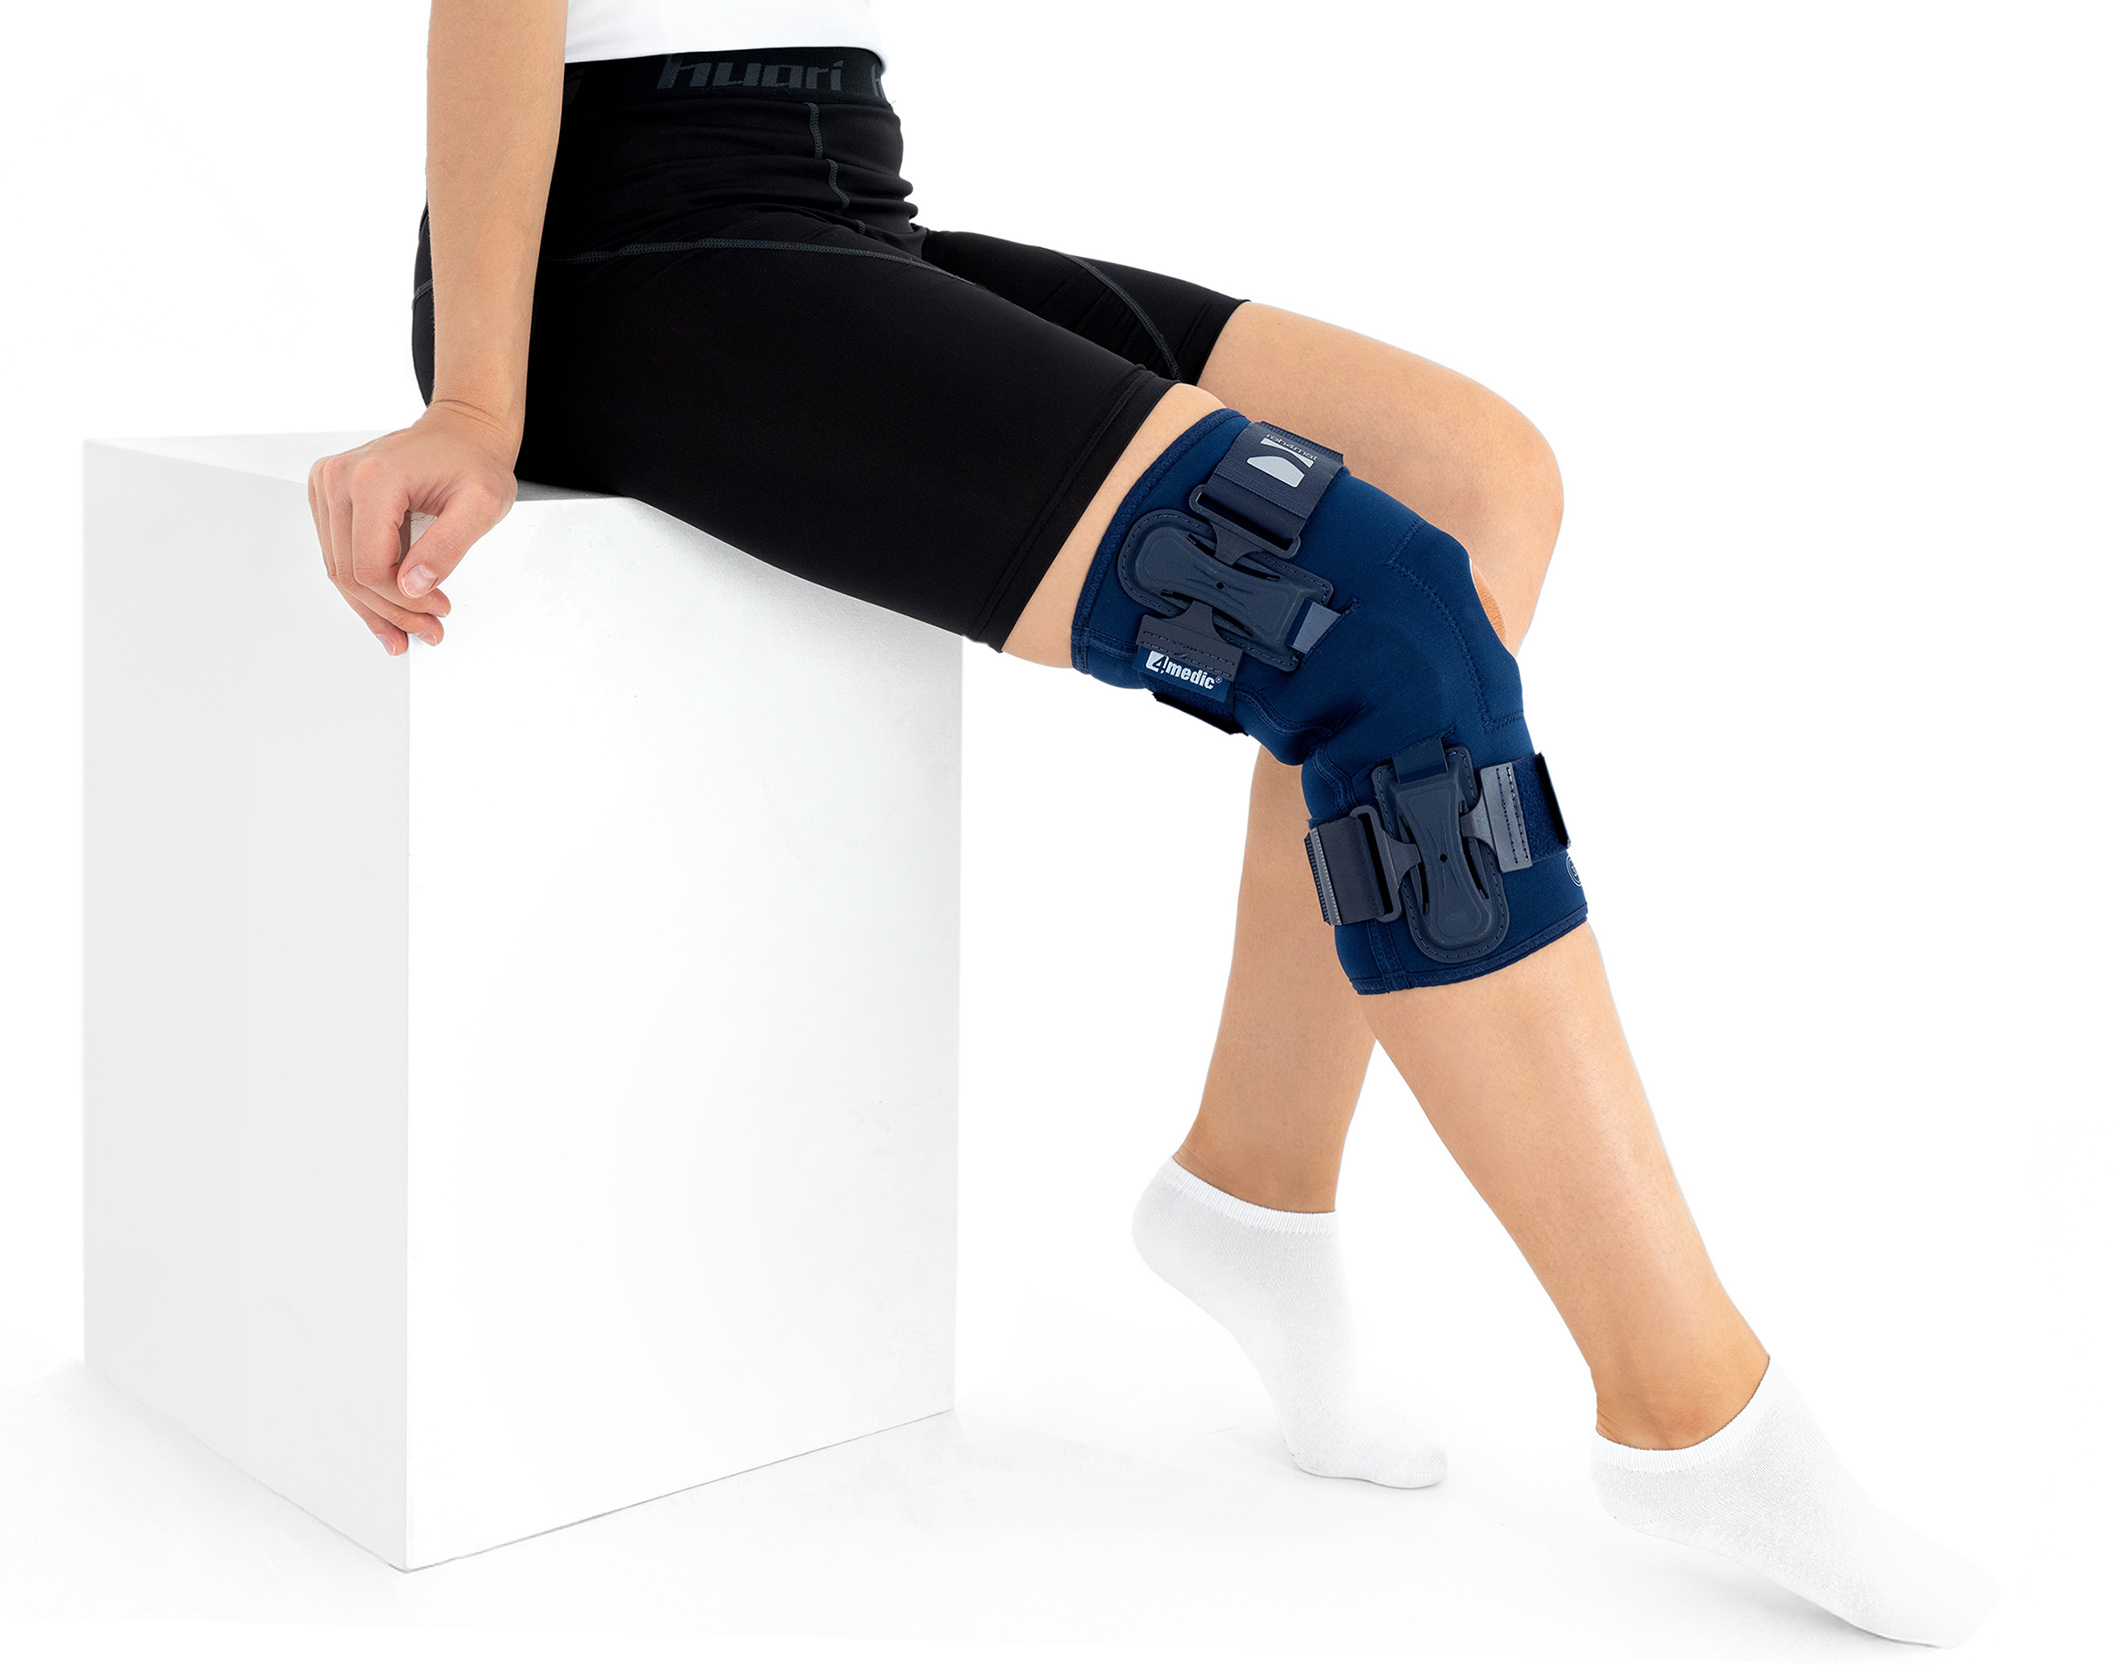

The OKD-40 professional knee brace provides stabilisation and controlled rehabilitation of the knee joint, with particular emphasis on patellofemoral stability.

The knee brace features a closed design, fully encompassing the knee joint, thigh, and lower leg. This structure increases lateral and anterior–posterior stability, prevents the brace from shifting during movement, and ensures even compression.

The OKD-40 hinged knee brace includes an anatomical patellar donut, which stabilizes the patella, maintains its correct tracking, and reduces patellofemoral overload. Thanks to this feature, the brace effectively reduces pain, prevents lateral patellar maltracking, and supports the treatment of chondromalacia and other conditions related to abnormal patellar alignment.

OKD-40 professional knee brace is equipped with durable lateral splints with dual-axis hinges for ensuring anatomical axial alignment of the knee and protect against uncontrolled joint displacement. The applied dual-axis knee hinges replicate the natural biomechanics of the knee joint, where rolling and gliding movements occur simultaneously during flexion and extension. The presence of two axes allows for improved control of this complex motion.

The hinges are integrated with the patented EASY FIT SOLUTION system, developed to further enhance the fit of orthopaedic braces to the anatomical contours of the body and the individual therapeutic needs of the user.

Manufactured from breathable, skin-friendly materials, the brace allows effective moisture management and prevents overheating, ensuring all-day comfort.

The OKD-40 patella knee support brace with dual-axis provides joint stabilisation while preserving natural knee biomechanics. It supports the treatment of knee sprains, patellar instability, and the rehabilitation process following injuries or orthopaedic procedures, increasing safety, comfort, and movement control during daily activities.